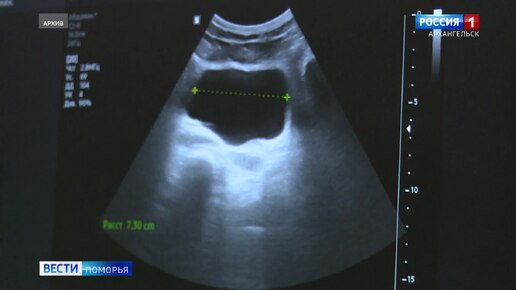

Завтра жители Поморья могут пройти бесплатное обследование почек